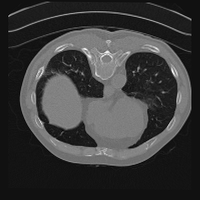

Exp. 3: Adult thorax data: To show the versatility of our approach we also apply it to adult thorax scans. For this experiment no organ specific training is performed but the whole volume is used. We evaluate reconstruction performance similar to Exp. 1 and Ti^^subscript𝑇𝑖\hat{T_{i}} prediction performance when ΩΩ\Omega is projected on an external plane, comparable to X-Ray examination using C-Arms. The latter provides insights about our method’s performance when applied to interventional settings in contrast to motion compensation problems. 60 healthy adult thorax scans were randomly selected, 51 scans used for ΩtrainsubscriptΩ𝑡𝑟𝑎𝑖𝑛\Omega_{train} and nine scans used for ΩvalidationsubscriptΩ𝑣𝑎𝑙𝑖𝑑𝑎𝑡𝑖𝑜𝑛\Omega_{validation}. Each scan is intensity normalised and resampled in a volume of 200×200×200200200200200\times 200\times 200 with spacing 1mm×1mm×1mm1𝑚𝑚1𝑚𝑚1𝑚𝑚1mm\times 1mm\times 1mm. Using the Fibonacci sampling method, 25 sampling plane of size 200×200200200200\times 200, evenly spaced between -50 and +50, were rotated over 500 normals. Training took approximately 20 hours for 60 epochs. Fig. 4c shows an example reconstruction result gaining 28dB PSNR with additional SVR. Ti^^subscript𝑇𝑖\hat{T_{i}} prediction takes approx. 20 ms/slice for this data.

Figure 4: (a): Comparison of a single slice from raw low-dose thorax CT data; (b): reconstruction based on SVRNet Ti^^subscript𝑇𝑖\hat{T_{i}} regression; (c): SVR initialized with SVRNet transformations after four iterations of SVR; (d): PSNR of (b) and (c) compared to (a). (e): shows a projection of an unseen pathological test CT volume as DRR and (e) shows a DRR at the location predicted by our method when presented with the image data in (e).

We use Siddon-Jacobs ray tracing [15] to generate Digitally Reconstructed Radiographs (DRRs) from the above described data. For training, we equally sample DRRs on equidistant half-spheres around 51 CT volumes at distances of 80cm, 60cm, and 40cm, between 90superscript90-90^{\circ} and 90superscript9090^{\circ} around all three co-ordinate axes. For validation, we generate 1000 DRRs with random rotation parameters within the bounds of the training data at 60cm distance from the volumetric iso-centre. We trained on healthy volunteer data and tested on nine healthy and ten randomly selected pathological volumes (eight lung cancer and two spinal pathologies). Our approach is able to predict DRR transformations relative to the trained reference co-ordinate system with an average translation error of 106mm and 5.6superscript5.65.6^{\circ} plane rotation for healthy patients, and 130mm and 7.0superscript7.07.0^{\circ} average error for pathological patients. An example is shown in Fig. 4e,f. Note that these values are good enough to robustly initialize intensity-based registration refinement. SVRNet prediction can be improved by generating a denser training data set, in particular, in more equidistant half-spheres.